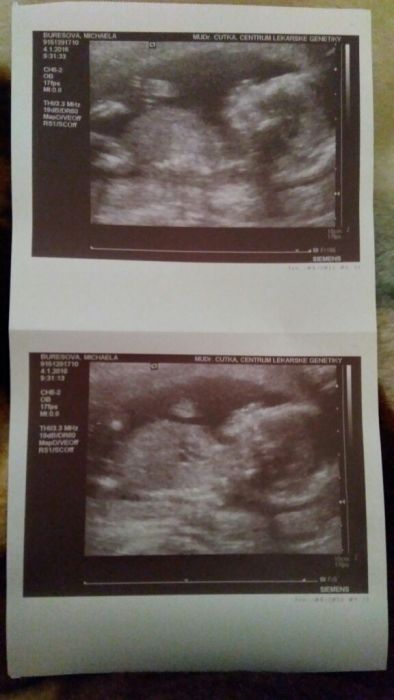

Ahoj holky, přidávám se trochu se zpožděním....Dnes jsem 17+4tt a termín porodu mám 10.6.2016. Ikdyž to podle doktora zatím není vůbec jisté, tak budeme pravděpodobně mít chlapečka. Jsem těhotná prvně....V posledních dench mě začaly trápit strie. Mazala jsem ElastiQ a včera jsem koupila ještě Bepanthen, kéž by se to zlepšilo. Nemáte s tím některá také zkušenost?Díky